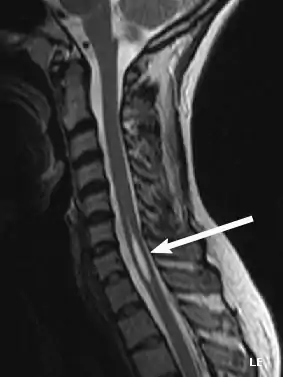

Physicians now use magnetic resonance imaging (MRI) to diagnose syringomyelia. The MRI radiographer takes images of body anatomy, such as the brain and spinal cord, in vivid detail. This test will show the syrinx in the spine or any other conditions, such as the presence of a tumor. MRI is safe, painless, and informative and has greatly improved the diagnosis of syringomyelia.[14][15][16][17][18][19][20][21][22][23][24][25]

Diagnostic technology is another area for continued research. MRI has enabled scientists to see the situation within the spine, including syringomyelia, before any symptoms appear. A new technology, known as dynamic MRI, allows investigators to view spinal fluid flow within the syrinx. CT scans allow physicians to see abnormalities in the brain, and other diagnostic tests have also improved greatly with the availability of new, non-toxic, contrast dyes.